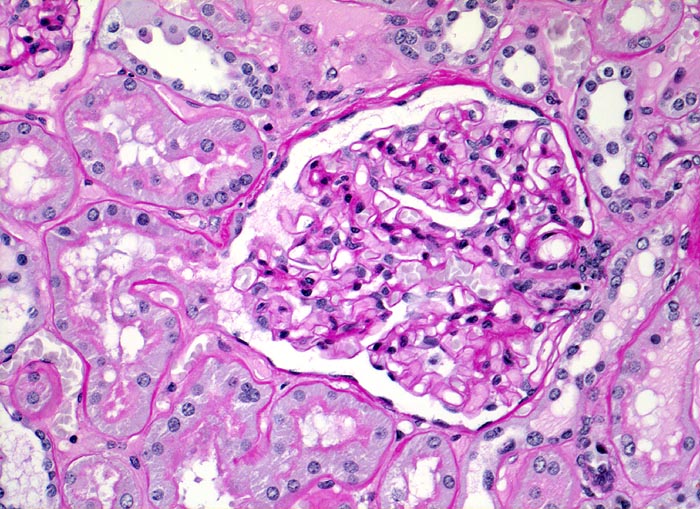

PathoPic ID 3443 - Normale Nierenrinde: Glomerulus mit Harnpol und Gefässpol.

Normale Nierenrinde: Glomerulus mit Harnpol und Gefässpol.

Unauffälliger Glomerulus mit

Harnpol (Hauptstück des proximalen Konvoluts) und

Gefässpol. Zarte glomeruläre Basalmembranen und normozelluläres Mesangium. Entzündungsfreier tubulointerstitieller Raum. Zarte tubuläre Basalmembranen.